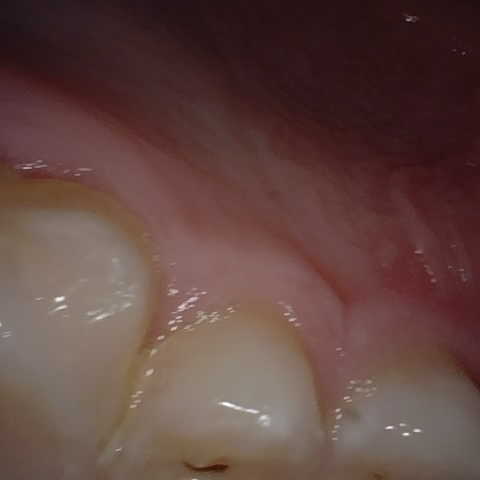

Annotated as "Good"